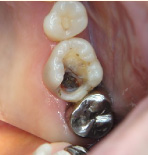

下の写真の一番左は実は治療前の写真です。痛みもなく一見問題なく入っている銀歯も除去してみると中に虫歯が。殺菌作用のある薬を詰めて治療中です。外からは分かりずらい虫歯も多いので定期検診がおすすめです。

- 治療前

- 除去

- 治療中